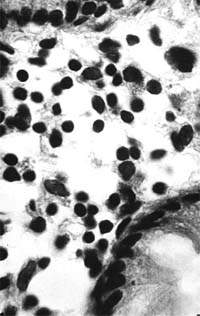

Рисунок 1. Слизистая оболочка толстой кишки при ротавирусном гастроэнтерите. Минимально выраженный катаральный колит. х 100.

Рисунок 2. Слизистая оболочка толстой кишки при ротавирусном гастроэнтерите. Минимальное содержание плазматических клеток в собственной пластинке, увеличение в ней числа макрофагов. х 400

В клинической практике врач нередко сталкивается с обстоятельствами (сомнительные результаты вирусологических и серологических исследований, случаи микст-инфекций), когда возникает необходимость в применении дополнительных методов для верификации диагноза. С этой целью может быть использован доступный для практического здравоохранения интрументальный метод исследования — ректороманоскопия с аспирационной биопсией слизистой оболочки толстой кишки. При гистологическом, морфометрическом и гистохимическом исследованиях биоптатов при ротавирусном гастроэнтерите выявляются характерные изменения в виде поверхностного минимально выраженного катарального колита с незначительной дистрофией эпителия (рис. 1), снижения числа серотонинсодержащих желудочно-кишечных эндокриноцитов (ЕС-клетки) в эпителиальном пласте кишечных желез, умеренной инфильтрацией собственной пластинки плазматическими клетками и увеличением в ней числа макрофагов (рис. 2). Эти особенности имеют дифференциально-диагностическое значение, поскольку отличаются указанным показателем от других острых кишечных инфекций, что может быть использовано в диагностически сложных случаях.